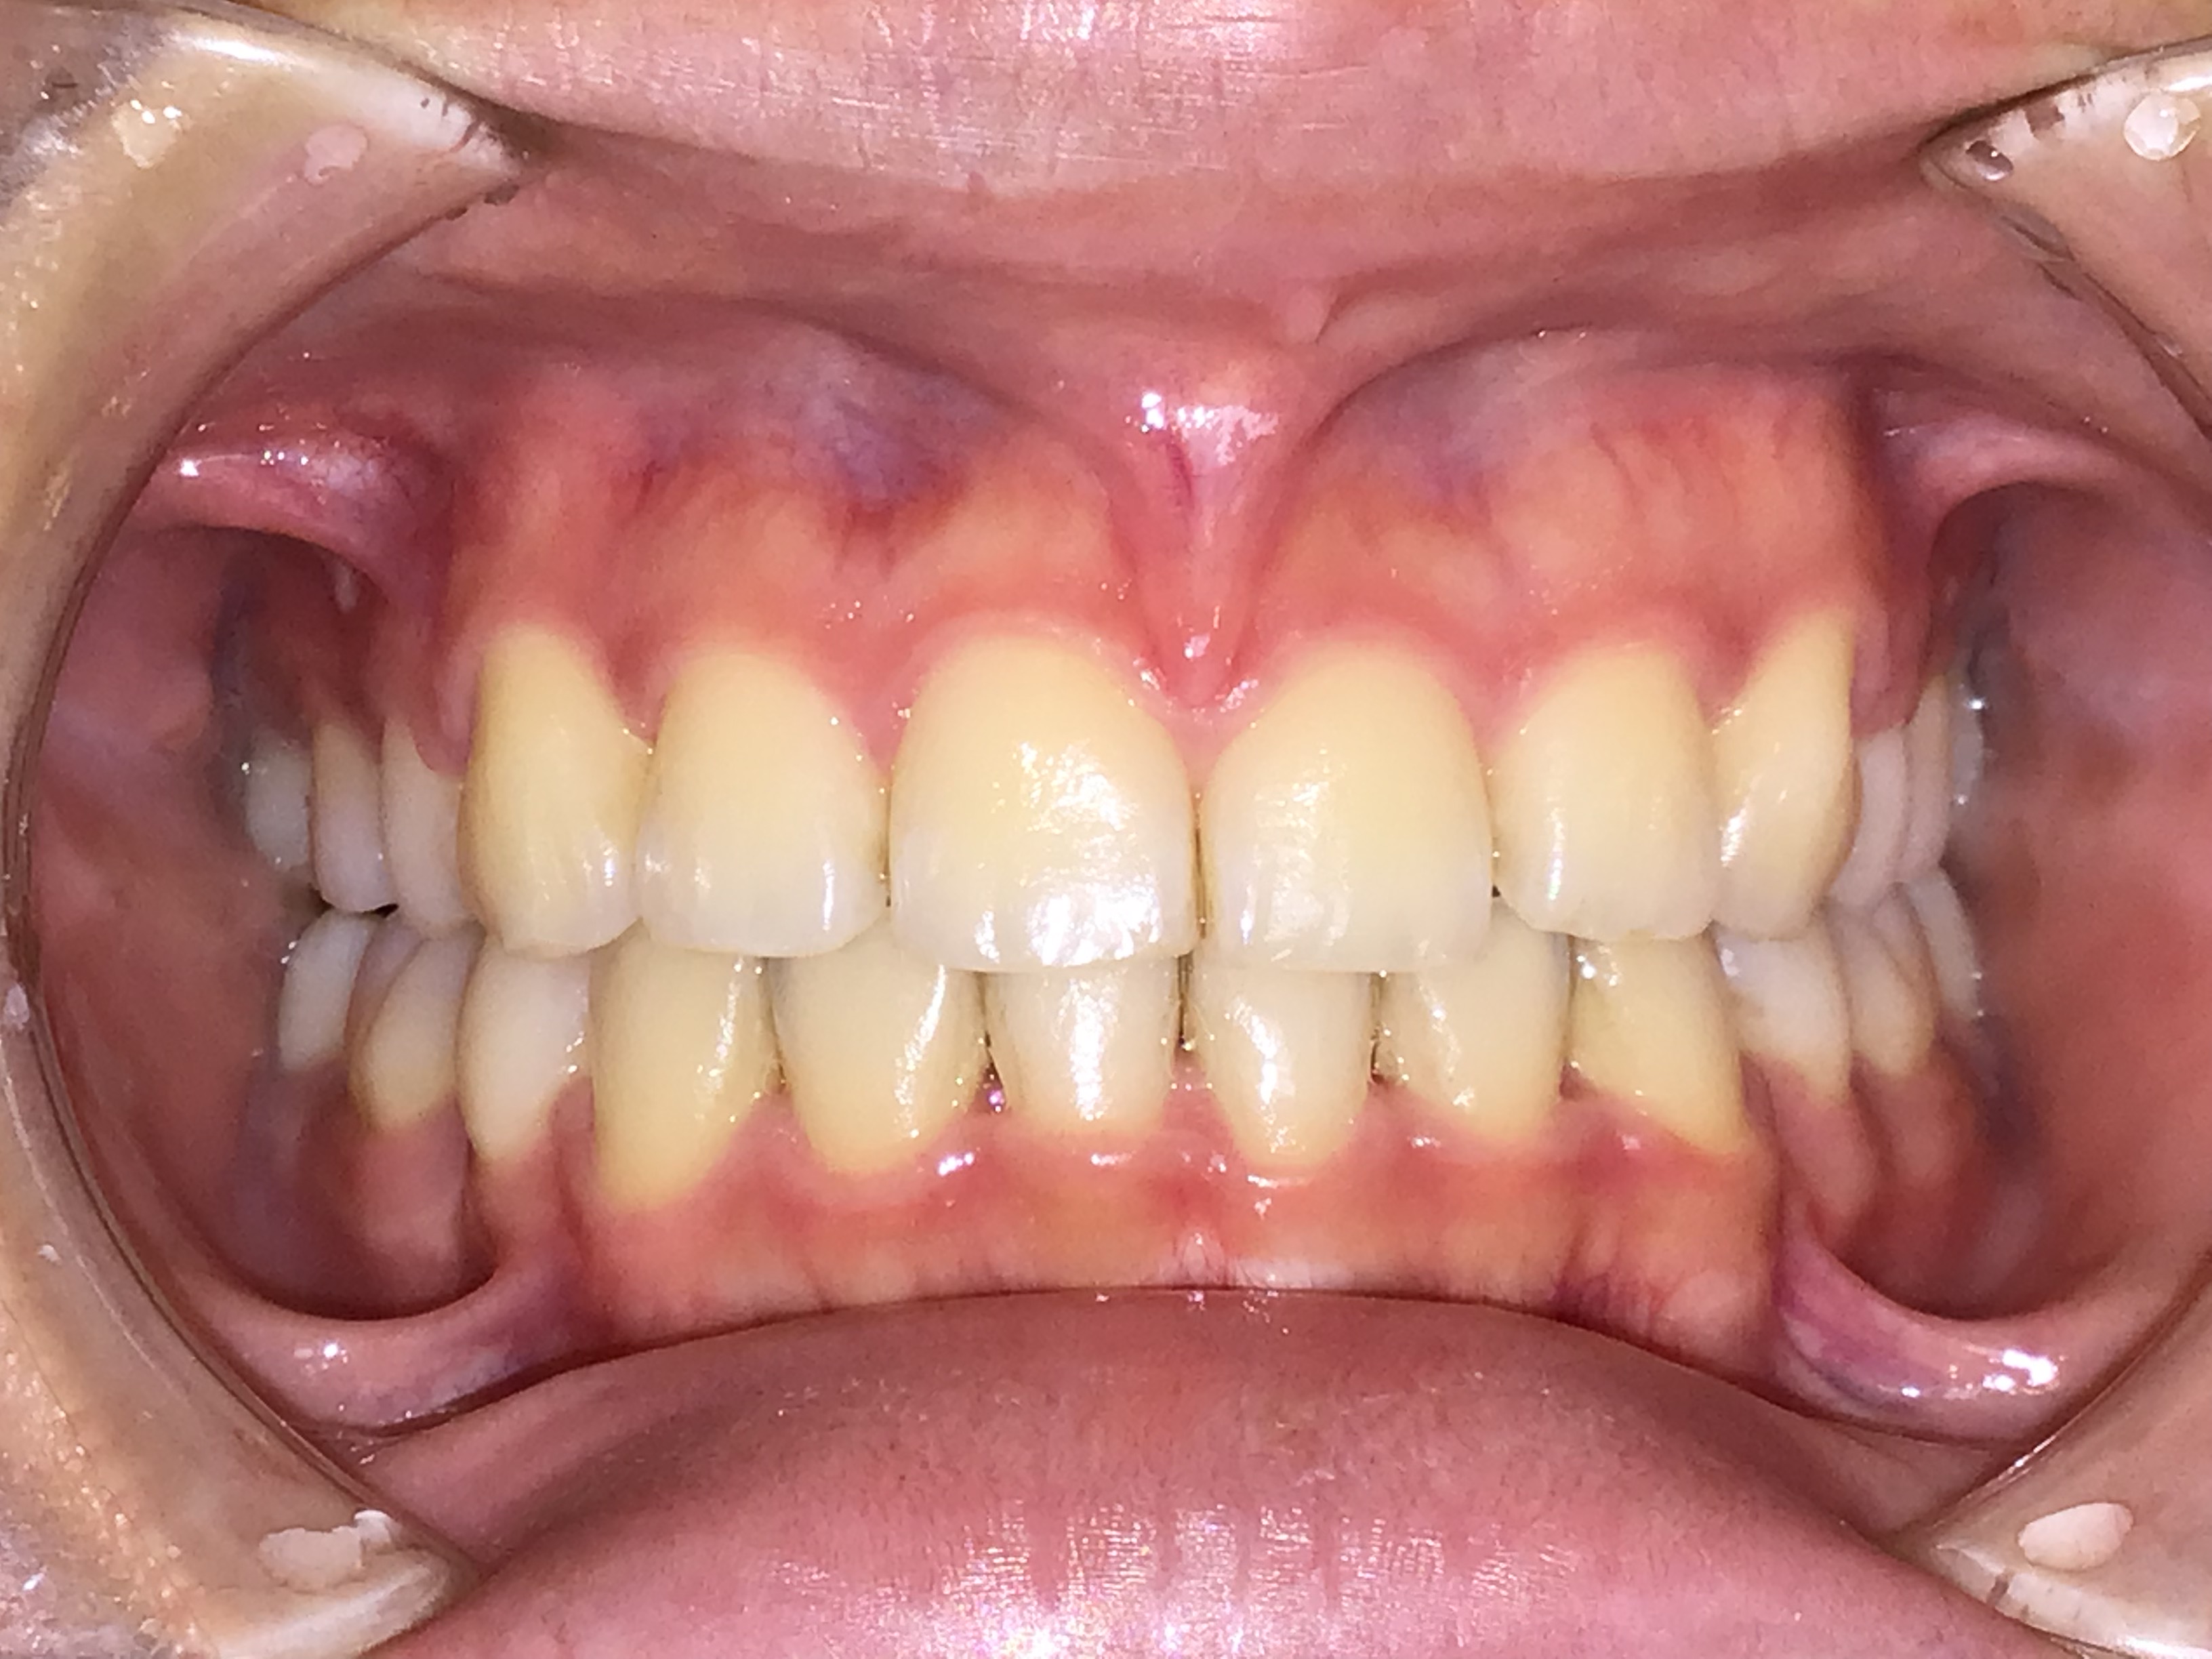

治療前 治療後 | 主訴 | 歯並びがでこぼこしている |

| 診断 | 歯列叢生症 |

| 初診時年齢 | 15歳2ヶ月 |

| 治療種別 | 本格矯正 |

| 外科処置 | 上顎左右第一小臼歯、下顎左第一小臼歯、右第二小臼歯の抜歯 |

| 主な治療装置 | マルチブラケット装置、矯正用アンカースクリューなど |

| 治療期間 | 3年7ヶ月 |

| 治療費 | 90万円(税別) |

| リスク・副作用 | 矯正装置による不快感や痛みが生じることがあります(数日〜1、2週間で慣れることが多いです)。歯の動き方には個人差があり、予想された治療期間が延長する可能性があります。歯を動かすことにより歯根が吸収して短くなることや、歯ぐきがやせて下がることがあります。治療中は装置が付いているため歯が磨きにくくなり、むし歯や歯周病のリスクが高まります。治療途中に金属等のアレルギー症状が出ることがあります。装置を外す時にエナメル質に微小な亀裂が入る可能性があります。装置が外れた後、保定装置を指示通り使用しないと後戻りが生じる可能性があります。治療後に親知らずが生えて凸凹が生じる可能性があります。 |